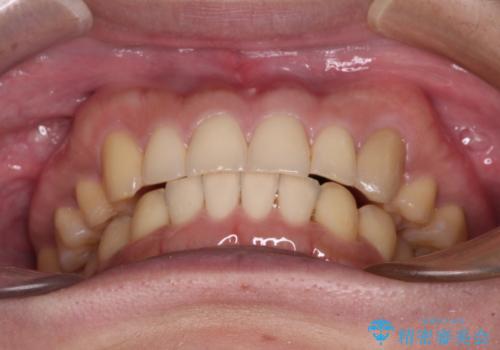

- 上顎の八重歯と前歯のデコボコを気にして来院された患者様です。

八重歯の移動量が多く、インビザライン単体での治療は困難と判断し、補助装置により八重歯移動後にインビザラインを用いることとしました。

上顎のみの抜歯矯正をインビザラインで行う場合、奥歯の前方移動がインビザラインでは苦手のため、奥歯の咬み合わせが不十分となることがあります。

今回の治療では終了時に奥歯は接触しているものの、接触の程度は物足りないものがある状態でした。今後保定期間に少しずつ奥歯の咬合を改善させていくことになります。